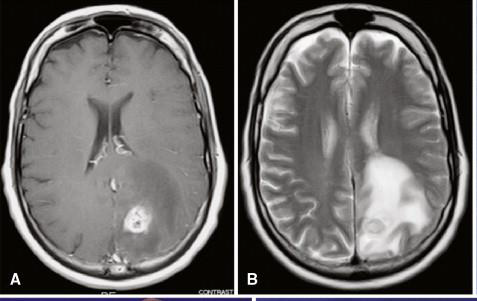

What caused this vasogenic edema?

Cerebral abscess